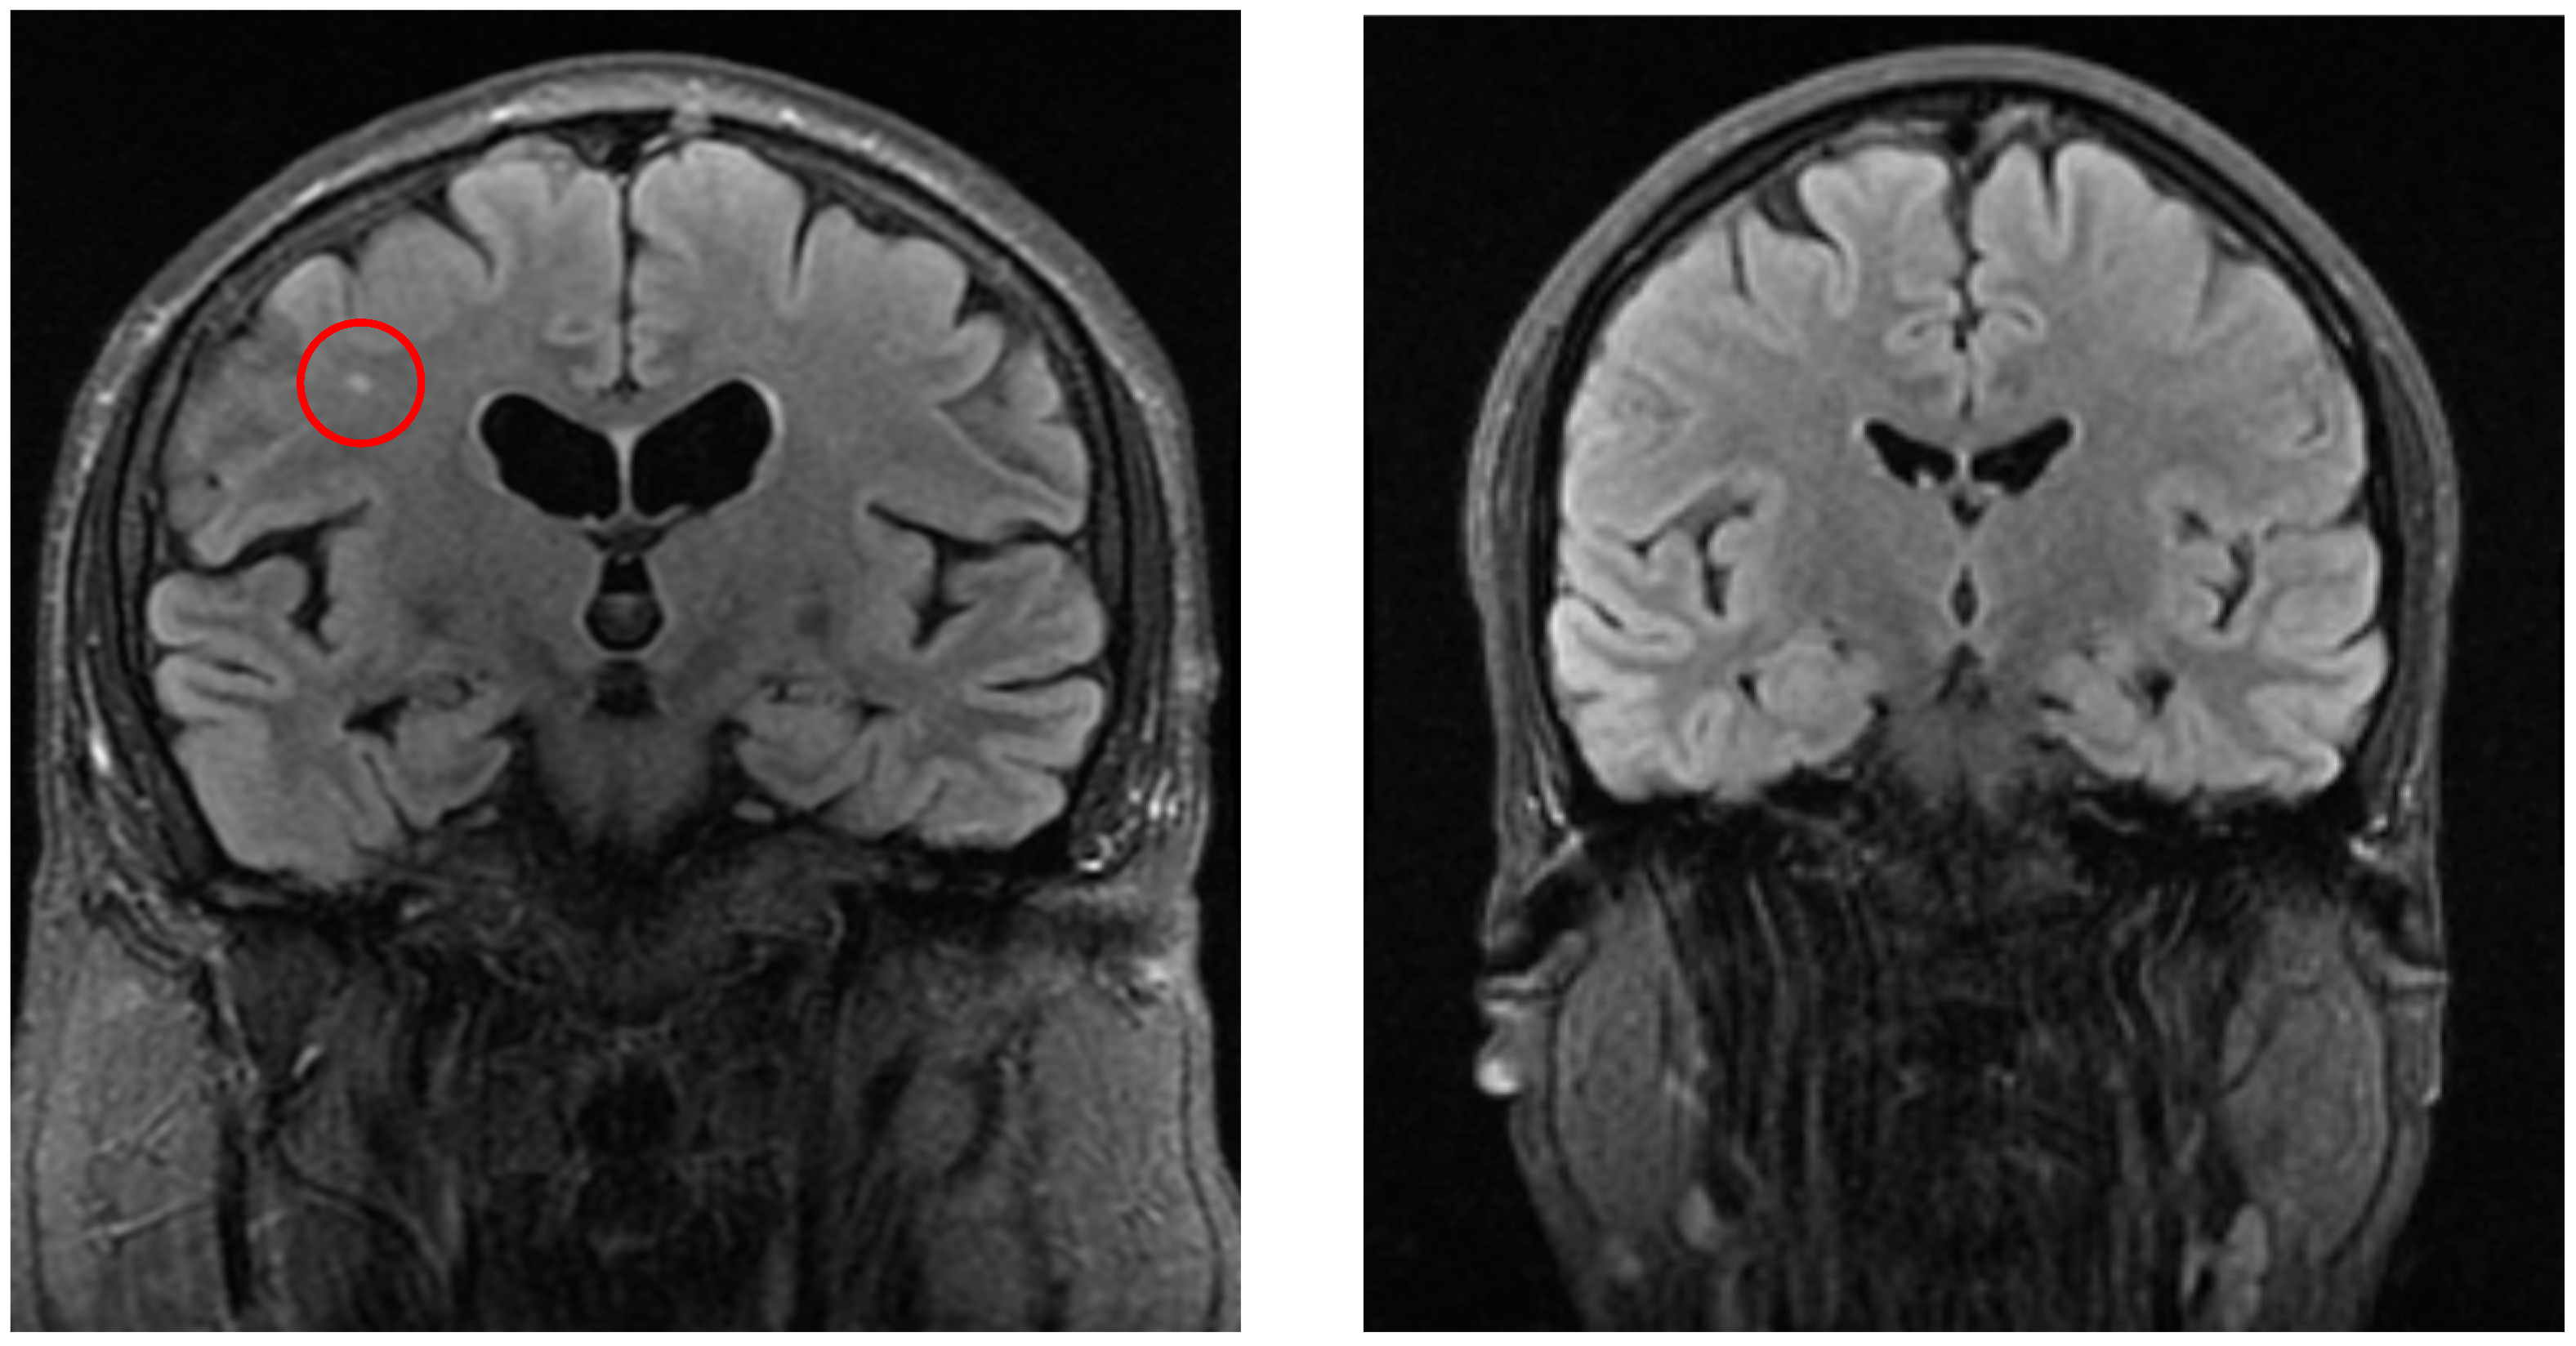

Significant differences were detected in white matter lesions (p = 0.001, see Figure 2), lacunar lesions (p = 0.047), Circle of Willis variation (p = 0.03), and sinusitis/sinus abnormalities (p = 0.005). Other MRI findings, including cortical atrophy, vascular lesion, and vascular encephalopathy, did not show statistically significant differences (p > 0.05).

Figure 2. The left image (coronal FLAIR) shows a white matter lesion (red circle) in a patient from the vertigo group, whereas the right image (coronal FLAIR) demonstrates a control patient without such lesions.